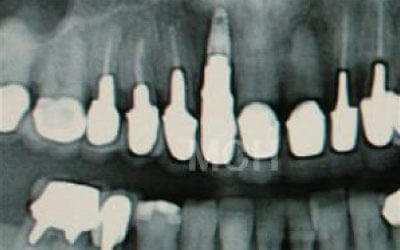

CTでは骨や歯の状態などを3次元で見ることができ、正確な距離を測ることも可能です。

骨の厚みや傾き、神経の位置などを事前にしっかり計測することで安全なインプラントが可能となります。